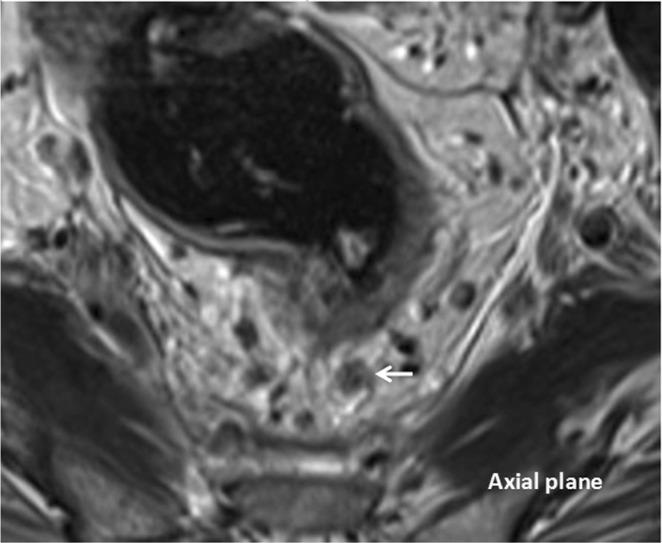

The purpose of this study was to evaluate the prognostic significance of the magnetic resonance imaging-detected extramural venous invasion (MR-EMVI), the depth of mesorectal extension (MR-DME), and lymph node status (MR-LN) in clinical T3 mid-low rectal cancer. One hundred and forty-six patients with clinical T3 mid-low rectal cancer underwent curative surgery were identified. Pretreatment high-resolution MRI was independently reviewed by two experienced radiologists to evaluate MR-EMVI score (0-4), MR-DME (≤4 mm or >4 mm), and MR-LN (positive or negative). The Cox-multivariate regression analysis revealed that the MR-EMVI was the only independent prognostic factor that correlated with overall 3-year disease-free survival (DFS) (p = 0.01). The survival analysis showed that patients with positive MR-EMVI, MR-DME > 4 mm, and positive MR-LN had a poorer prognosis in the overall 3-year DFS (HR 3.557, 95% CI 2.028 to 13.32, p < 0.01; HR 3.744, 95% CI:1.165 to 5.992, p = 0.002; HR 2.946, 95% CI: 1.386 to 6.699, p < 0.01). By combining MR-EMVI with MR-DME or MR-LN, the prognostic significance was more remarkable. Our study suggested that the MR-EMVI, MR-DME, and MR-LN were the important prognostic factors for patients with clinical T3 mid-low rectal cancer and the MR-EMVI was an independent prognostic factor.

本研究旨在评估磁共振成像检测到的外膜静脉侵犯(MR-EMVI)、直肠系膜延伸深度(MR-DME)和淋巴结状态(MR-LN)在临床 T3 中低位直肠癌中的预后意义。我们确定了 146 例接受根治性手术的临床 T3 中低位直肠癌患者。两名经验丰富的放射科医生对术前高分辨率 MRI 进行独立评估,以评估 MR-EMVI 评分(0-4 分)、MR-DME(≤4mm 或>4mm)和 MR-LN(阳性或阴性)。Cox 多因素回归分析显示,MR-EMVI 是唯一与总 3 年无病生存率(DFS)相关的独立预后因素(p=0.01)。生存分析显示,MR-EMVI 阳性、MR-DME>4mm 和 MR-LN 阳性的患者总 3 年 DFS 预后较差(HR 3.557,95%CI 2.028-13.32,p<0.01;HR 3.744,95%CI:1.165-5.992,p=0.002;HR 2.946,95%CI:1.386-6.699,p<0.01)。通过将 MR-EMVI 与 MR-DME 或 MR-LN 相结合,预后意义更加显著。我们的研究表明,MR-EMVI、MR-DME 和 MR-LN 是临床 T3 中低位直肠癌患者的重要预后因素,MR-EMVI 是独立的预后因素。